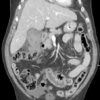

Vỡ túi mật

» Thông tin: Nam giới – 80 tuổi.

» Lâm sàng: Chấn thương.